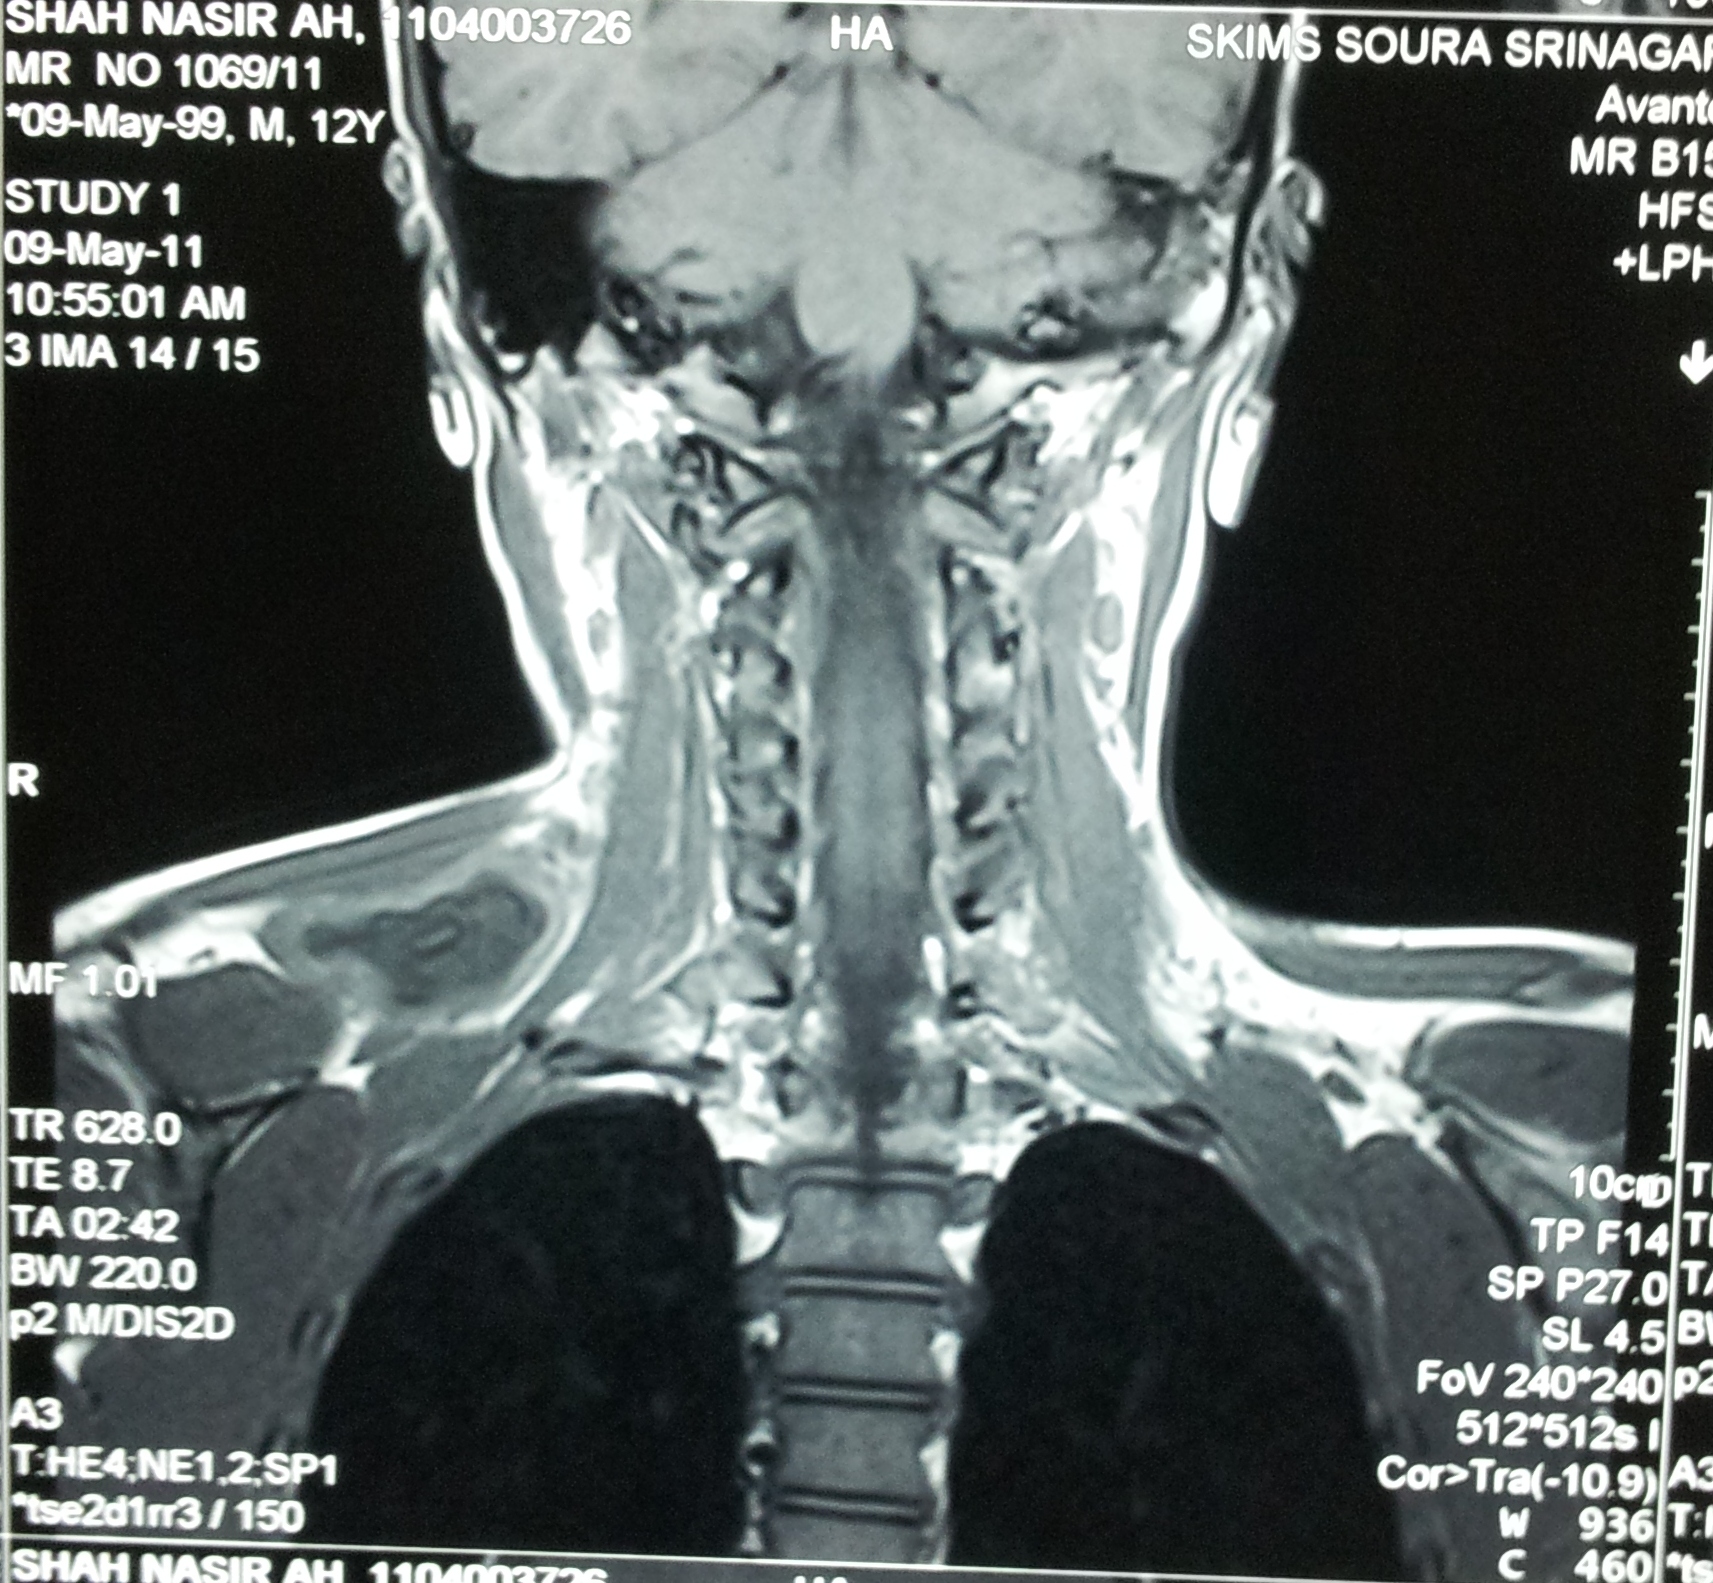

A case of hydatid cyst involving posterior triangle of neck in a 10 year old male child is reported. Diagnosis was confirmed by MRI. Surgical excision of the cyst was done. Hydatid cyst in posterior triangle should be considered one of the possibilities in evaluating a cystic swelling in this region.